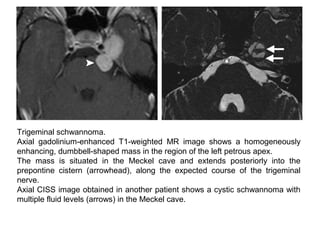

Trigeminal schwannoma.

Axial gadolinium-enhanced T1-weighted MR image shows a homogeneously

enhancing, dumbbell-shaped mass in the region of the left petrous apex.

The mass is situated in the Meckel cave and extends posteriorly into the

prepontine cistern (arrowhead), along the expected course of the trigeminal

nerve.

Axial CISS image obtained in another patient shows a cystic schwannoma with

multiple fluid levels (arrows) in the Meckel cave.